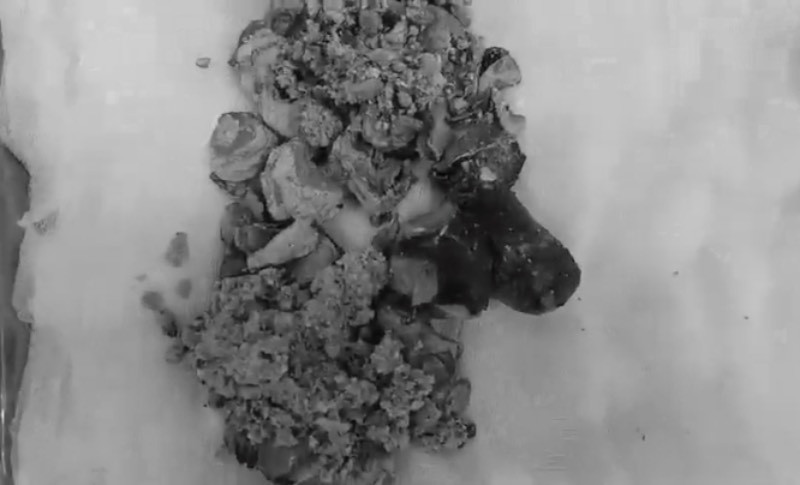

Bác sĩ đã quyết định mổ mở để lấy sỏi thận. Quá trình phẫu thuật, các bác sĩ bóc tách được viên sỏi san hô dài tới 20cm, nặng 500g. Bác sĩ Liên cho biết trường hợp này may mắn vì chức năng thận đã phục hồi, bệnh nhân không phải chạy thận chu kỳ. Sau 10 ngày điều trị theo dõi, sức khỏe bệnh nhân đã hồi phục và ra viện.